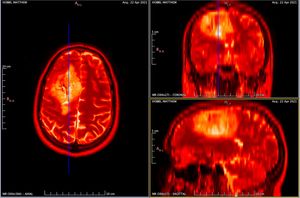

In the above image you can see my MRI scan. It's essentially an orthogonal view of my head, with each of the panels represents a different axis:

- Left panel: Top of my head (Axial view)

- Top right: Front to back of my head (Coronal view)

- Bottom left: Side of my head (Sagittal view)

The solid blue line you see in the views is the current plane I have selected to see. As you move this plane, all three images change accordingly. Notice how the blue line on the axial view (left panel) matches that of the coronal view (top right) in terms of position. The resulting image in the sagittal view (bottom left) is the image that corresponds with this selection I have made.

It's so incredibly clever and absolutely fascinating (to me at least)! I spent the best part of 2-3 hours looking at my own brain scans. I wish I knew what it all meant, but I plan on quizzing the experts when I get the chance. I'd like to write a blog post all about it in the future. So, watch this space!

For those interested in doing the same the tools I used are:

Horos takes it a step further, as it allows you to view your scan in 3D, and even export an animation to show all your friends at the next soirΓ©e you attend! So yes, if you ever fancy looking at your own insides in detail, remember you can request your CT and MRI scan data!